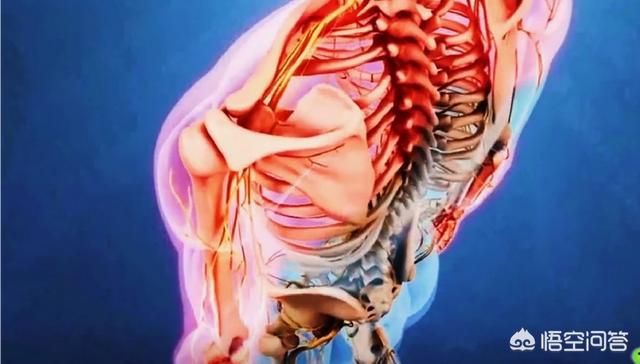

脊髓型颈椎病多数都是由于颈椎的椎间盘突出、椎体后缘的骨刺、韧带的骨化、黄韧带肥厚等原因严重的压迫了颈椎椎管内的脊髓而导致脊髓缺血出现的一些症状。很多患者如果确诊为脊髓型颈椎病会出现手笨拙无力、走不了直线、容易摔倒、出现痉挛步态的一些表现,有一些严重的患者甚至会出现排便困难。